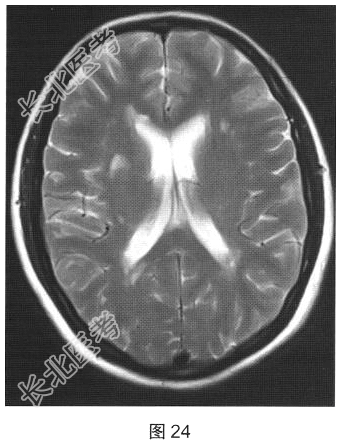

- [材料题] 患者女性,40岁,渐进性肢体无力6个月。颅脑MRI检查如图23、图24所示。

- 简答题1、根据MRI表现,可能的诊断是?